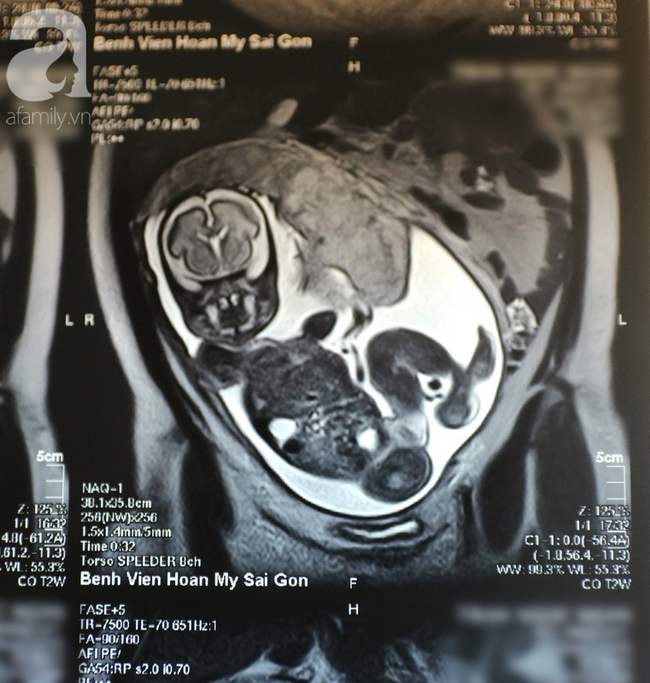

Trước tình hình đau bụng không dứt của thai phụ, sau khi hội chẩn ngay tại khoa Cấp cứu, các BS thống nhất cho bệnh nhân chụp MRI vùng bụng để xác định bệnh. Kết quả cho thấy ruột thừa bệnh nhân bị viêm với đường kính 10 mm, chưa vỡ.

Bệnh nhân được chỉ định phẫu thuật nội soi cắt ruột thừa. Sau 1 giờ thực hiện phẫu thuật, ca mổ đã thành công. Thai phụ nhanh chóng hồi phục sức khỏe và đã được xuất viện sau 2 ngày điều trị.

ThS.BS Nguyễn Quang Luật, người tiếp nhận và phẫu thuật cho bệnh nhân chia sẻ, viêm ruột thừa ở phụ nữ mang thai là phổ biến. Nhưng ở phụ nữ mang thai lớn (3 tháng cuối thai kỳ) lại ít gặp và rất khó chẩn đoán, vì khi đó tử cung to, đẩy ruột thừa ra khỏi vị trí thường gặp nên chẩn đoán thường bị chậm trễ.

"Nghiên cứu ở Hoa Kỳ cho thấy, siêu âm bụng chẩn đoán được viêm ruột thừa ở phụ nữ mang thai 3 tháng cuối chỉ chiếm 3-5% trường hợp, chẩn đoán chỉ bằng cách khám lâm sàng có thể sai đến 42%.

Chính vì vậy cần có sự hỗ trợ của các phương tiện chẩn đoán hình ảnh hiện đại như MRI, là phương tiện gần như không gây hại cho mẹ và thai nhi mới giúp bác sĩ chẩn đoán được chính xác bệnh, nhằm tránh phải mổ nhầm những trường hợp không cần thiết phải mổ, tránh những biến chứng cho mẹ và thai nhi".